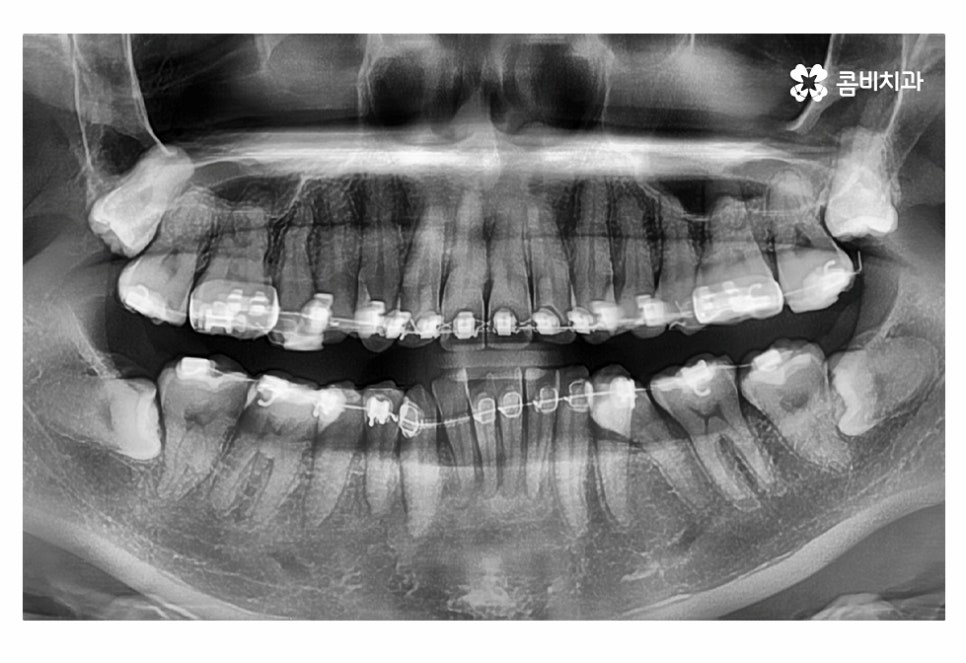

오늘 보실 교정 사례 역시도 윗니는 치아 설측교정으로

진행이 되고 아랫니는 일반적인 순측교정으로 진행되었으며

이러한 치아교정 방법을 콤비교정이라고 부르고 있어요.

사진으로 보시는 환자분의 경우 윗니에 비해

아랫니가 좀 더 불규칙하다는 것을 알 수 있는데요.

위 사진에서 보시는 것과 같이 윗니의 경우 치아설측교정으로

진행이 되고 있기 때문에 교정 장치가 눈에 띄지 않고 있어요.

오늘 사례의 환자분은 아랫니의 치열이 불규칙하고

교합을 고려할 때 전체교정을 진행해야 했지만